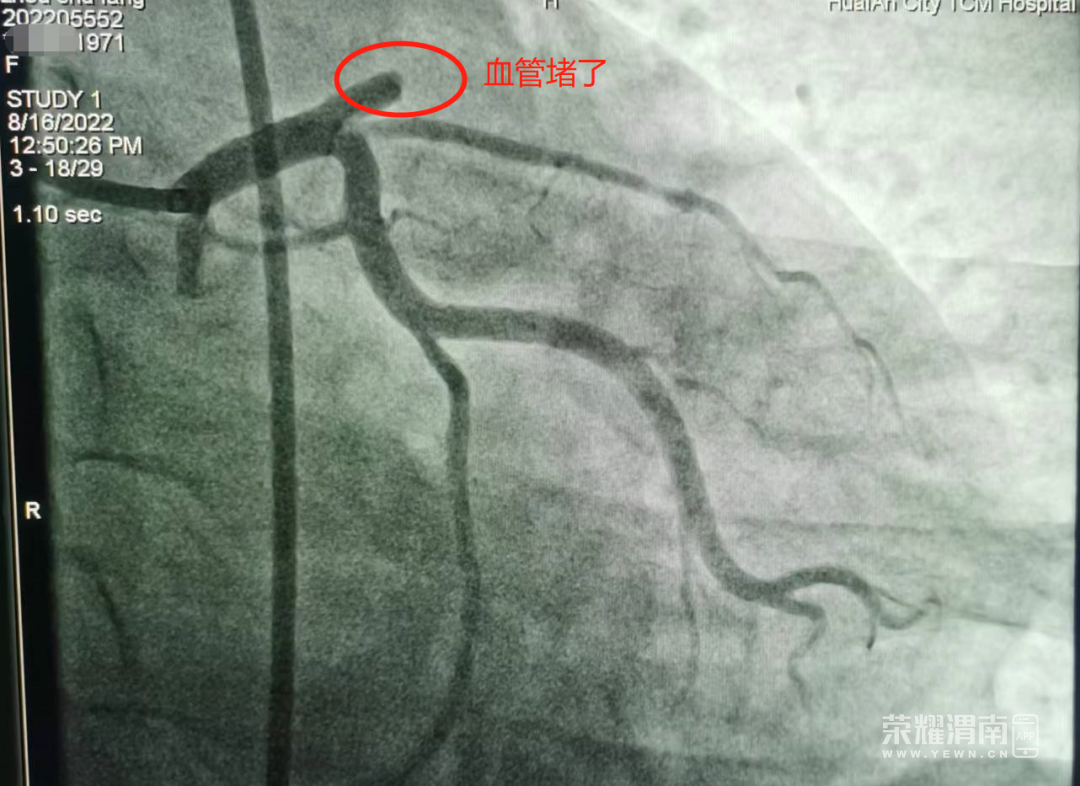

医生为患者进行心脏冠脉造影

发现患者心脏左前降支

已完全闭塞

随即进行介入溶栓治疗

并植入心脏支架